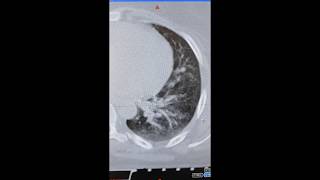

Статистика и эпидемиология онкологических заболеваний